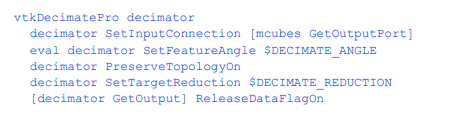

减少三角形的数量

等值面算法生成的三角形通常比我们渲染所需的要多。在这里,我们通过消除位于用户指定距离内的三角形顶点来减少三角形计数,这些三角形顶点是由相邻顶点构成的平面。我们保留三角形的任何边,这些边被认为是“特征”。